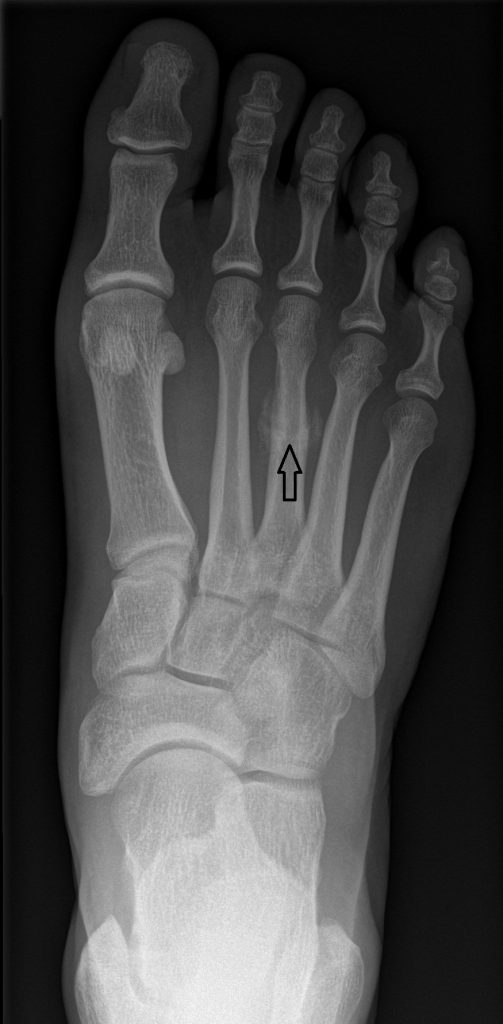

Marsfractuur

Een marsfractuur wordt ook wel stressfractuur, stressbreuk of vermoeidheidsbreuk genoemd. Een marsfractuur is een micro botbreuk van een of meerdere middenvoetsbeentjes. Deze botbreuk kan ontstaan door het lopen van lange wandelingen of een mars. Ook bij marathon lopers komt een marsfractuur voor.

Door overbelasting van de middenvoetsbeentjes, kunnen er microscheeurtjes in het bot ontstaan. Als de microscheurtjes aanwezig zijn en men loopt toch langdurig door, kan het middenvoetsbeentje scheuren.

Een marsfractuur is pas 2 weken na de breuk zichtbaar op een röntgenfoto. Als u dus meteen na de wandeling veel pijn heeft en een röntgenfoto laat maken, zal de breuk niet meteen zichtbaar zijn. Dit komt omdat de scheurtjes vaak klein zijn en na 2 weken is er pas zichtbaar dat er extra bot wordt aangemaakt op de plek van de kleine breuk. (zie afbeelding onder)

Bij Podologie Arnhem, maken de podoloog meteen een echo, waardoor we sneller een diagnose kunnen stellen. De podoloog zal u adviseren om tijdelijk niet, of zo weinig mogelijk te wandelen. Ook zal hij een steunzool maken om de aangedane plek drukvrij te leggen.